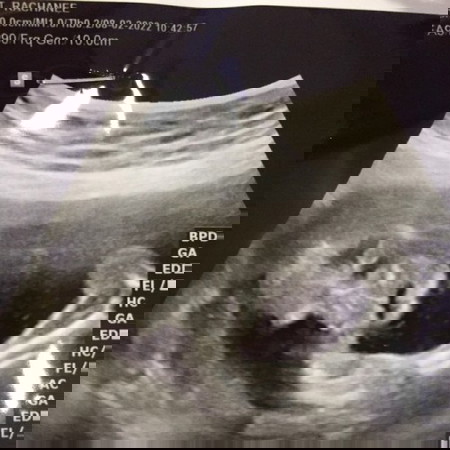

สวัสดีครับแม่ๆ ผมชื่อ ด.ช.ภูริณัฐ ภิญโญฤทธิ์ ชื่อเล่น เรอา กำหนดคลอด 6/7/65 คลอดจริง 17/5/65 อายุครรภ์ 37w+2d น้ำหนัก 3230 กรัม ผ่าคลอด แข็งแรงทั้งแม่และลูกค่ะ เช้าวันที่ 16/5 แม่ผมปวดฉี่เลยไปเข้าห้องน้ำ แต่มีมูกเลือดออกมา (ท้องแม่ผมปั้นบ่อยทุกๆวัน แต่ไม่มีวี่แววจะคลอด ลุงหมอให้นอนโรงพยาบาลกินยาระงับคลอด 2 วัน และกลับบ้านก็ได้แต่สอดยาระงับคลอด) พอดีกับเป็นวันที่ลุงหมอนัดแม่ตรวจครรภ์ ลุงหมอตรวจปากมดลูกและติดเครื่อง แม่เริ่มปวดท้อง ปากมดลูกเปิด 1 เซ็น ลุงหมอให้แม่กลับบ้านสอดยาถี่ขึ้น เพราะอายุครรภ์ผมยังน้อยอยู่ แต่แม่ไม่กลับเพราะคิดว่าไม่น่าจะพ้นคืนนี้ ตี 5 ของวันที่ 17/5 แม่ปวดท้องถี่ แม่ปวดฉี่ลุกเข้าห้องน้ำ ตอนตี 5.30 น. เลือดแม่ออกเยอะมากๆ พร้อมมีน้ำเดิน แม่รีบไปหาหมอทันที และผ่าคลอดผมออกมา เวลา 10.10 น. ของวันที่ 17/5 ครับ #ท้องสอง #ผ่าคลอด